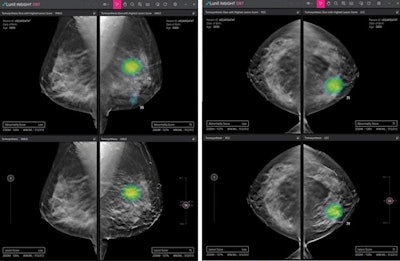

Lunit Insight DBT was designed to accelerate reading by identifying 3D slice images with suspicious breast lesions from among multiple images. Its new CT software is called Lunit Insight Chest CT, which automatically generates the location, type, volume, and axial diameter of detected nodules.

Lunit is launching its Lunit Insight DBT software at RSNA 2021. Image courtesy of Lunit.Lunit will offer demonstrations of Insight DBT and Lunit Insight Chest CT at the company's booth during the meeting, with an official launch planned next year, the company said.